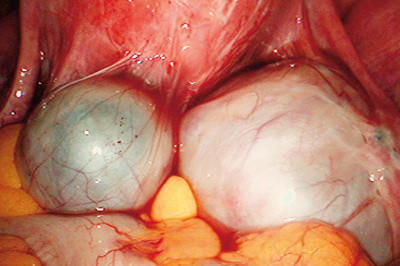

Kirurgisk teknikk ved endometriomer avhenger av mange forhold som pasientens alder, fertilitetsønske, men ikke minst av endometriomets størrelse. Vi skiller gjerne mellom små (mindre enn 0,5 – 1 cm i diameter), middels store (opptil 5 cm i diameter) og store endometriomer (over 5 cm i diameter). I tillegg kommer andre dimensjoner ved bilaterale endometriomer og bilaterale adherente endometriomer (kissing ovaries (fig 3)).

Med dyp endometriose (dypt infiltrerende endometriose, DIE) omtales endometriose som affiserer tarm, vesentlig rektosigmoideum, vagina og urinblære. Tilstanden er mindre vanlig enn peritoneal og ovarial endometriose, men fører ofte til uttalte symptomer og redusert livskvalitet (22) – (25). Dyp endometriose ses ikke sjelden samtidig med bilaterale, adherente endometriomer (kissing ovaries) (fig 3) og til dels også ved utbredt peritoneal endometriose.